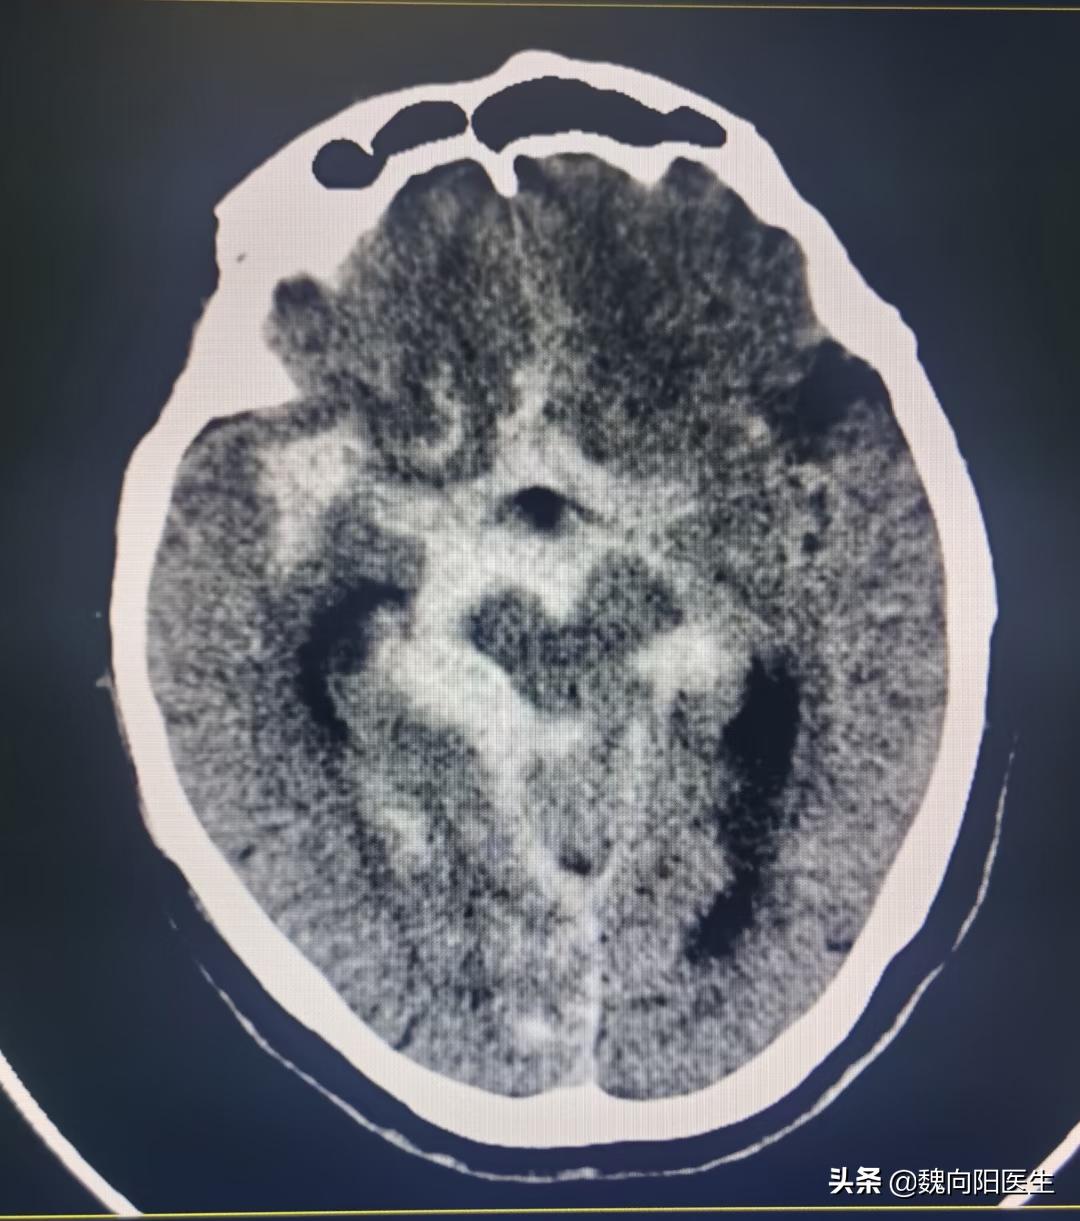

蛛网膜下腔出血

蛛网膜下腔出血,此时老太已经处于昏迷状态,属于Hut-hess分级4级,死亡率30-50%,况且老太年龄已经78岁了,属于高龄患者。

温馨提示:蛛网膜下腔出血属于出血性脑卒中的一种,是一种严重危及生命的疾病,90%以上的蛛网膜下腔出血是由于颅内动脉瘤破裂所导致。对于自发性蛛网膜下腔出血患者,一定要检查脑动脉,脑血管造影是脑动脉检查的金标准。